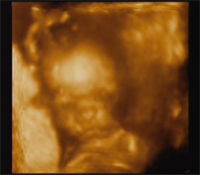

Sajna a fütyit nem lehet "kézzel" helyre tenni, mert neki nem letapadás van, hanem valódi szűkület, amit csak sebészeti úton lehetne kezelni. DE!! Minket inket inkább a műtét módja aggaszt....Úgy csinálják, hogy az egész bőrt eltávolítják, tehát nem lesz gond a húzogatással, tisztán tartással, magyarán körülmetélik!!

Én még csak hagyján, de a párom nagyon ellenzi! Azt mondja, a mi kultúránkra ez nem jellemző....Szóval most ott tartunk, hogy pénteken még elvisszük egy másik dokihoz véleményezésre, nem lehetne -e máshogy......

Persze nem akarunk mi okoskodni, ha más orvosok is ezt tartják jónak, akkor marad ez......